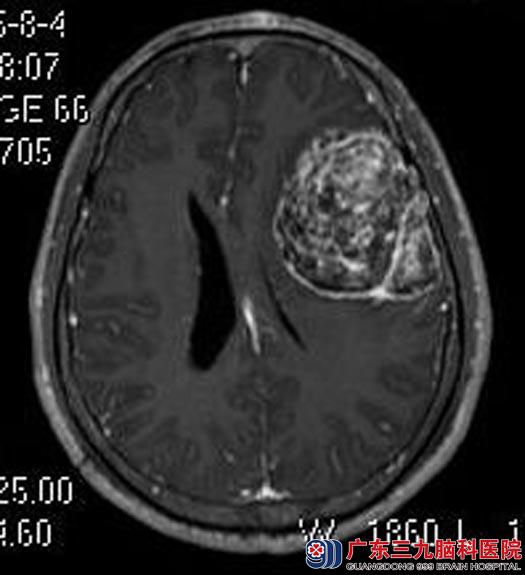

广东三九脑科医院进一步头颅MR检查提示:左侧额颞部占位性病变,大小约5.2cm×6.9cm×6.5cm,考虑脑膜瘤。

脑膜瘤对药物和放射治疗均不敏感,手术切除是最佳治疗方法。完善相关检查后,由综合神经外科鲁明主任主刀,在全麻下行左侧额部脑膜瘤切除术,术中显微镜下见肿瘤呈红色,质韧、血供丰富,边界清,予以全切,手术顺利。术后李先生自诉反应及记忆力明显较前好转。术后病理结果提示:混合型脑膜瘤(WHO I级)。